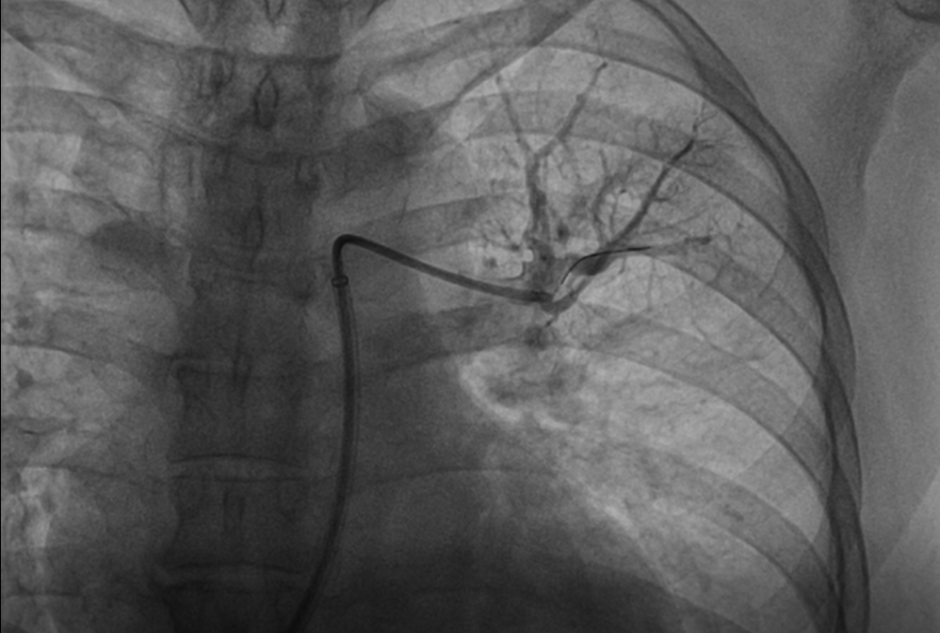

患者慕名至我院后,我科专家进一步对其进行了相关检查,最终诊断为:慢性血栓栓塞性肺动脉高压。心内科周亚峰副院长、陈弹主任、赵良平主任及团队成员进行深入讨论,并邀请呼吸科、血管外科与介入科等进行多学科(MDT)会诊,最终决定对其进行右心导管及肺动脉造影检查,结果提示肺动脉收缩压52mmHg,平均肺动脉压33mmHg,左右各肺动脉及其分支多发栓塞,可见多处血栓影及马赛克征。对右肺动脉A3、左肺动脉A1+2、左肺动脉A9行球囊扩张术,扩张后复查造影远端血流恢复良好。手术后患者的症状得到明显改善,心功能逐渐恢复,住院5天后平稳出院。出院后患者继续进行家庭氧疗、抗凝、利奥西呱降肺动脉压力等治疗,并密切随访中。随访至今,患者情况良好。

行球囊扩张后